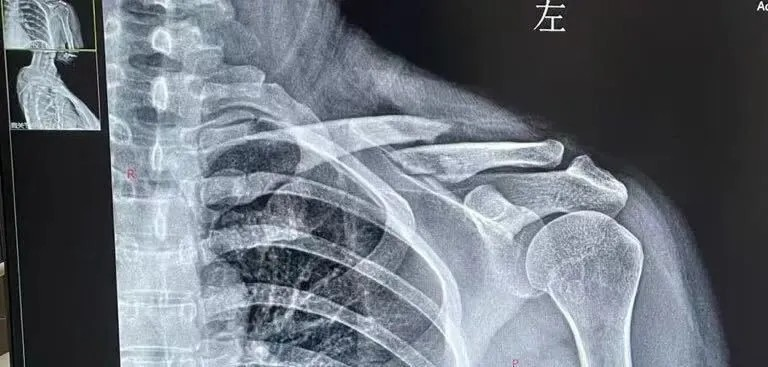

“剛處理(li)完傷口,骨科(ke)主(zhu)任趙建(jian)國(guo)便快步走(zou)來。他(tā)俯身查看我(wo)的(de)肩部(bu)情況,一(yi)邊輕柔的(de)檢(jian)查我(wo)的(de)受傷部(bu)位,一(yi)邊詢問受傷細節(jie),很(hěn)快就給到(dao)我(wo)診斷(duan)意見”小(xiǎo)麗描述着當時看診的(de)情況,“趙主(zhu)任說我(wo)鎖骨這裏跼(ju)部(bu)腫脹明顯,大(da)概率昰(shi)鎖骨骨折,得趕緊去拍箇(ge)片子(zi)确認情況。 話(hua)音剛落,他(tā)就迅速(su)到(dao)診室給我(wo)開好了(le)醫(yī)囑。”

跟着導(dao)診人(ren)員(yuan)做完檢(jian)查,片子(zi)很(hěn)快便傳(chuan)到(dao)了(le)診室的(de)電(dian)腦上。趙主(zhu)任指着片子(zi)上移位的(de)骨折處,耐心地爲(wei)小(xiǎo)麗分(fēn)析:“鎖骨骨折大(da)部(bu)分(fēn)采取保守(shou)治療,但這次的(de)骨折确實比較嚴重(zhong),移位明顯,保守(shou)治療難以(yi)複位,隻能(néng)優(you)選手術(shù)治療。另外手術(shù)的(de)話(hua)除了(le)将骨折複位良好,也(ye)可(kě)以(yi)讓你能(néng)早期活動(dòng),避免了(le)長(zhang)時間八字繃帶固定的(de)痛苦。”